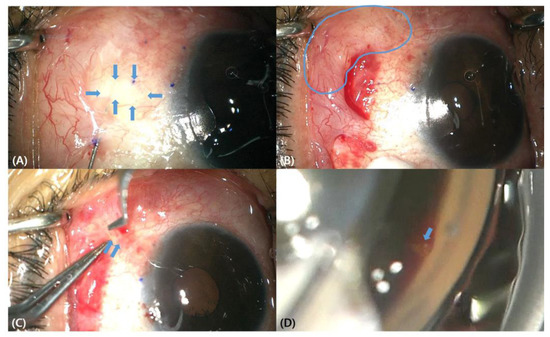

On the first day following surgery, the IOP was 10 mmHg, and moxifloxacin, prednisolone, and mydriatic eye drops were administered 4 times a day. On the 4th day after surgery, the IOP was 14 mmHg, and the vision had fully recovered to the preoperative level of 20/20. On the 11th day after surgery, the IOP was 21 mmHg, so once-daily use of preservative-free timolol/dorzolamide eye drops was initiated, and the IOP was maintained at 16 → 14 → 12 mmHg (1 → 3 → 6 months after surgery, Figure 3). Using slit-lamp examination of the bleb morphology, a localized avascular bleb was observed. Checking the morphology of blebs using OCT, a high, sparse wall was observed during the all follow-ups (Figure 4). The lengths of the fluid-filled cavity parallel and perpendicular to the section line at 6 months were 3.065 mm and 3.555 mm. The estimated size of the bleb was 34.21 mm2.

This study adhered to the principles of the Declaration of Helsinki. Written informed consent for the report and photographs was obtained from the patient. Postoperative blebs were imaged using slit-lamp photography and a Spectralis OCT (Heidelberg Engineering GmbH, Heidelberg, Germany) on postoperative day 1, week 1, week 2, and months 1, 2, 3, and 6, as described elsewhere. Briefly, a total of 41 section scans were aligned along with the parallel line at the point where the XEN tip was located. Images with quality scores higher than 25 were included in the final qualitative analysis. The maximum bleb height was selected and measured within the 41 sections that were obtained at each visit [4].

Figure 4. Bleb morphology using slit-lamp photos and AS-OCT imaging at postoperative day 1 (A), day 4 (B), day 14 (C), month 1 (D), month 3 (E), respectively. Note that the bleb morphology observed using slit-lamp photography exhibits characteristics of a localized avascular nature, while the bleb morphology observed using anterior segment optical coherence tomography (AS-OCT) demonstrates characteristics of a high sparse wall type. Please note that blue dashed lines represent the same location of each OCT section.